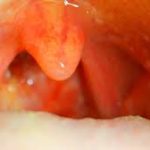

Tonsil muayenesi Kızarıklık, bademcik büyümesi, bazen beyaz püskürme Tonsil itilir, peritonsiller bölgede şişlik ve yanak/yan duvarda çıkıntı

Asimetri Genellikle simetrik Tonsiller arasında asimetri (etkilenen tarafta daha belirgin)

Ağız içi asimetri, uvula deviasyonu

• Ağız içinde bir taraf şişmiş/itilmiş görünür

• Uvula (dil ucunun arkası) karşı tarafa deviye olabilir